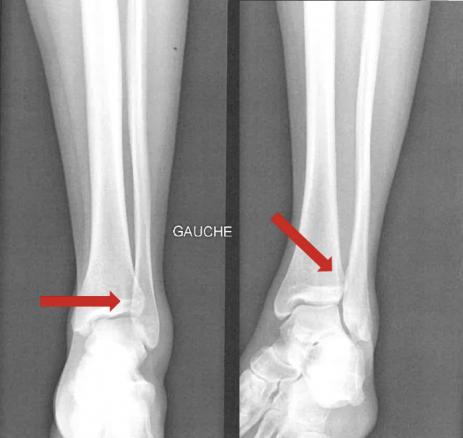

Une IRM confirme l’entorse grave dite « de la syndesmose », avec rupture complète du ligament tibiofibulaire antéro-inférieur (LTFAI) et de la membrane interosseuse (fig. 2 et 3 ), mais le ligament tibiofibulaire postéro-inférieur (LTFPI) est intact. L’absence de diastasis tibiofibulaire au bilan radiologique complémentaire classe la lésion en stade 2 (fig. 4).

En cas de suspicion clinique, les radiographies initiales de face et de profil, en charge, permettent de classer la lésion en cherchant un diastasis tibiofibulaire dont les critères d’interprétation sont les suivants :

– espace clair médial (normal inférieur à 4 mm) ;

– espace clair tibiofibulaire (normal entre 3 et 6 mm sur un cliché de face) ;

– superposition tibiofibulaire (normale supérieure à 5 mm sur un cliché de face stricte, ou supérieur à 1 mm sur un cliché en rotation interne de 20 ° [incidence de mortaise]).2

En cas de doute, le cliché comparatif controlatéral peut aider.